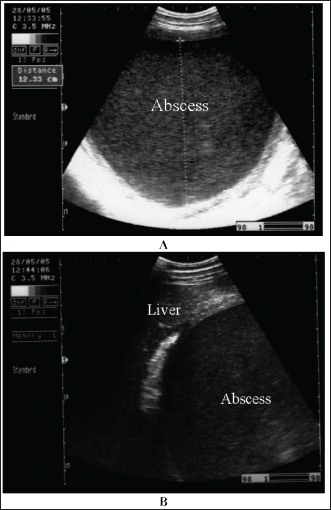

Abdominal abscesses

Intra-abdominal abscessation is not common in adult horses (Aleman et al., 2003; Recknagel et al., 2012) or in foals (Valdes and Johnson, 2005). In a 15-year-study, 40 horses with intra-abdominal masses were studied; 3 of them (7.5%) had mesenteric abscesses (Recknagel et al., 2012). The pathogenesis of abdominal abscessation in horses is presumably similar to that in ruminants (Aleman et al., 2003). It was not possible to determine the cause of the abdominal abscess in the present case. In addition, in equines, the abscess likely formed as a direct extension of a hematogenous infectious process, similar to the development of mesenteric abscess in a bull with chronic peritonitis (Elce, 2006). Several pathogens are considered causative agents of abdominal abscessation, such as Rhodococcus equi, Streptococcus equi subsp. equi, Corynebacterium pseudotuberculosis, Clostridium novyi type A, Blastomyces dermatitidis, and Fusobacterium necrophorum. Pseudomonas aeruginosa can also induce mesenteric abscesses in equines (Arnold et al., 2012; Tharwat et al., 2024c). Equines with abdominal abscesses are usually admitted with a history of fever, weight loss, colic, inappetence, and signs of depression of various durations (Tharwat et al., 2024c).

Abdominal abscess was strongly suspected on the basis of ultrasonographic findings (Fig. 20). The differential diagnoses include abdominal neoplasia. Ultrasonography is also useful for percutaneous needle aspiration for bacteriologic evaluation and facilitates intralesional antibiotic treatment and drainage because the thick abscess capsule prevents the spread of antibiotics (Tharwat et al., 2024c) (Figs. 21 and 22). For large abscesses, transcutaneous aspiration of pus should be performed under ultrasound guidance, as reported in cattle (Mohamed et al., 2002; Mohamed et al., 2003a,b,c; Mohamed and Oikawa, 2008). The ultrasound-guided percutaneous drainage of abdominal abscesses has several advantages. First, the animal should not be anesthetized. Second, surgery is not required, and consequently postoperative drawbacks will not develop. Third, percutaneous drainage is typically cost-effective. Fourth, percutaneous ultrasound-guided drainage can be performed promptly after diagnostic ultrasound is performed because the methodology does not require any particular planning or preparation and can be completed quickly if the examiner is experienced. Complications associated with ultrasound-guided percutaneous aspiration of the abscess in the present case were not encountered (Tharwat et al., 2024c). Follow-up after pus aspiration confirmed the treatment response, reduction in abscess size, and recovery (Figs. 23 and 24).

Fig. 20. Ultrasonograms of an 8-year-old Thoroughbred mare with abdominal abscess. Image A shows a sonogram obtained at admission (day 0) in which a mass with a thick echogenic capsule with homogenous and echogenic internal contents was identified. The mass was located close to the liver, deforming its right lobe margins B.